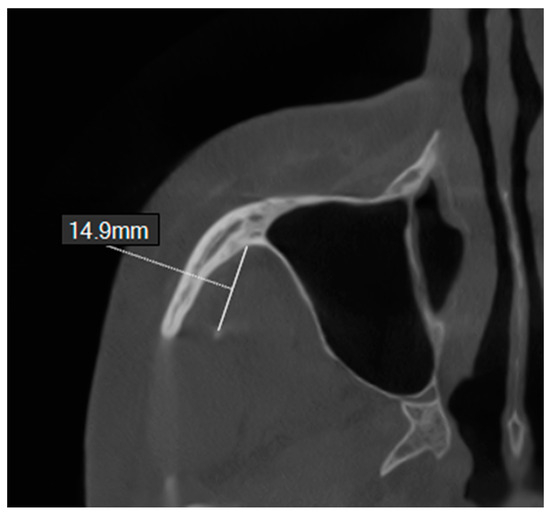

- Length of the coronoid process (Cor-L). This was evaluated along the long axis of the coronoid process. The distance between the tangent to the sigmoid notch and the tip of the coronoid process was measured.

- Length of the condylar process (Con-L). This was analyzed along the long axis of the condylar process. The distance between the tangent and the sigmoid notch and the tip of the condylar process was measured.